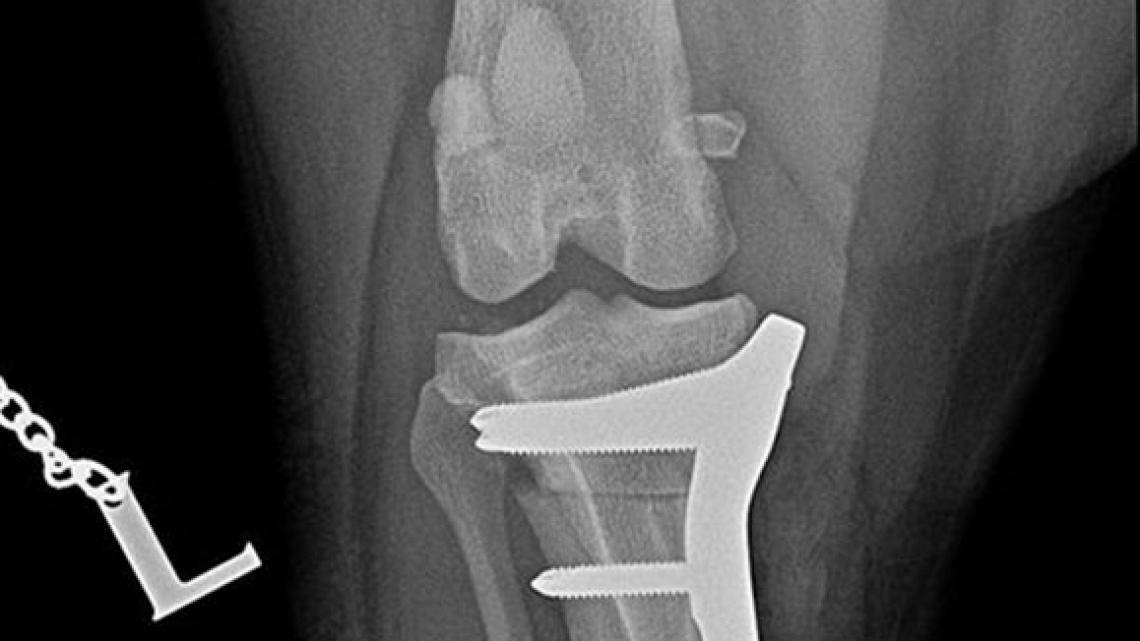

Shar-pei, cruciate ligament rupture surgery, TPLO with small pre-contoured polyaxial plate.

Sawed with R21 blade. Temporary fixation with 1,4 mm K-wire through the plate’s micro hole, which helps untill the locking poliax screws are driven in.